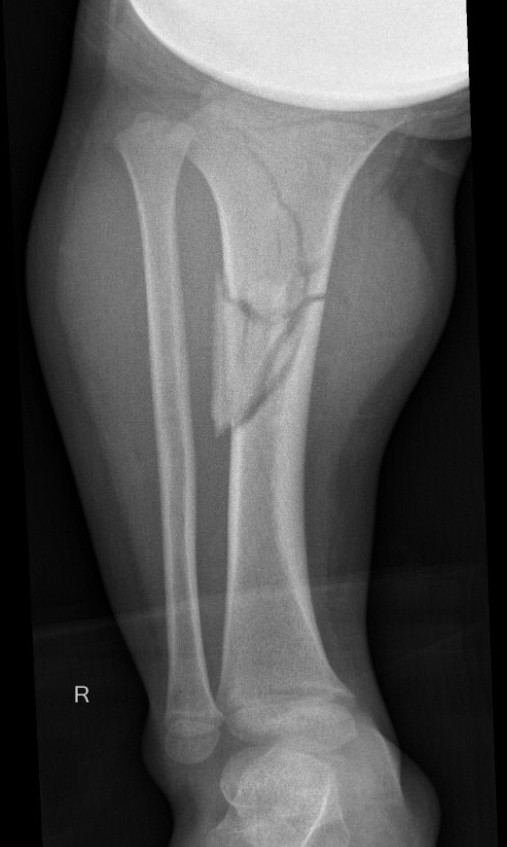

Displaced Tibial Shaft Fractures

Proximal Metaphyseal Tibial Fracture / Cozen's Fracture

Issue

- may develop long term valgus alignment

- due to medial epiphyseal overgrowth / periosteum medially